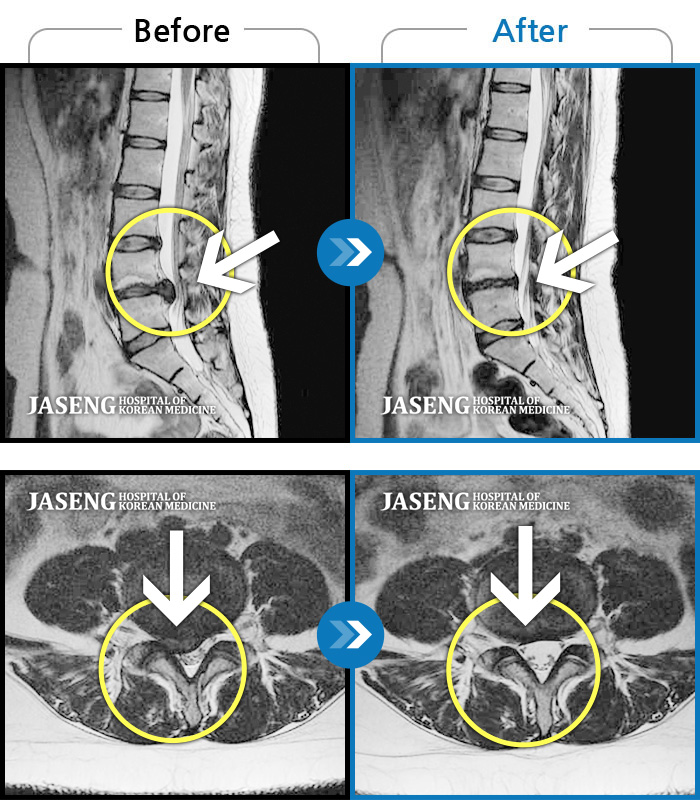

허리디스크

잠실 · 한상욱 원장

허리, 우측 엉치와 다리 후면 및 발끝까지 저림과 통증이 심하고 힘까지 빠진다.

촬영시기

2022.06.15 ~ 2022.11.11

2022.12.02